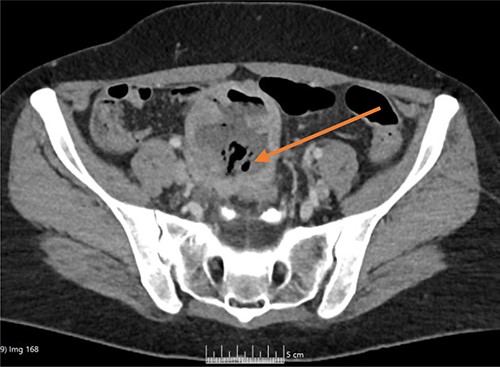

Once admitted to the haematology department, she was examined and was found to have a soft, non-tender abdomen with no signs of peritonism, and all her other systemic examinations were normal. Given the vague abdominal symptoms and blood profile, she was subjected to a CT scan of her chest, abdomen and pelvis (CT CAP). The scan reported a lower abdominal/pelvic thick-walled fluid and gas-filled structure that measured 5 × 7 × 6 cm lying adjacent to the urinary bladder with a likely fistulous tract to the overlying loops of bowel. A small amount of free fluid and non-specific stranding of fat was seen in the pelvis. No pulmonary or metastatic nodules were seen (Figs 1 and 2).

CT axial image, with arrow showing the midline lower abdominal/pelvic thick-walled fluid and gas-filled structure that measured 5 × 7 × 6 cm.